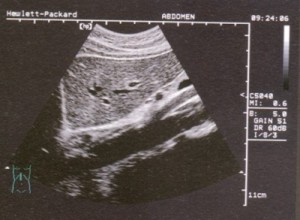

3.腹部超音波檢查:抽血檢查雖然能反應病人肝功能的狀況,但對於肝硬化或肝癌卻無法提供明確的訊息,尤其是部份肝硬化及肝癌的患者,其肝功能檢驗結果有時都還在正常範圍內,而且可能毫無症狀。所以抽血檢驗並配合超音波檢查是有其必要性的。